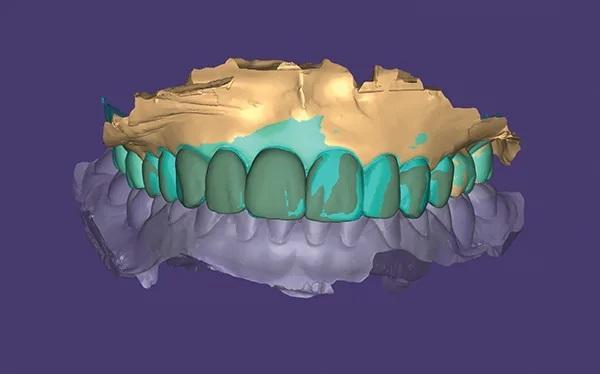

В программном обеспечении dental CAD (DentalCAD, exocad) был создан новый клинический случай и выбраны элементы, которые необходимо было спроектировать. Имплантат был выбран и подобран из библиотеки имплантатов для обеспечения совместимости с корпусами (колпачками) сканирования. Ранее разработанный макет улыбки был импортирован в качестве дополнительного файла в формате STL, чтобы служить руководством для проектирования окончательных реставраций. Зуб с естественной текстурой был выбран из предложенной библиотеки в программном обеспечении dental CAD, и был выполнен индивидуальный дизайн абатмента для реставрации с опорой на имплпнтат. Как только дизайн был завершен, был создан файл STL и экспортирован для изготовления окончательных реставраций (Фото 11).

Фото 11. Показан цифровой дизайн финальных реставраций.